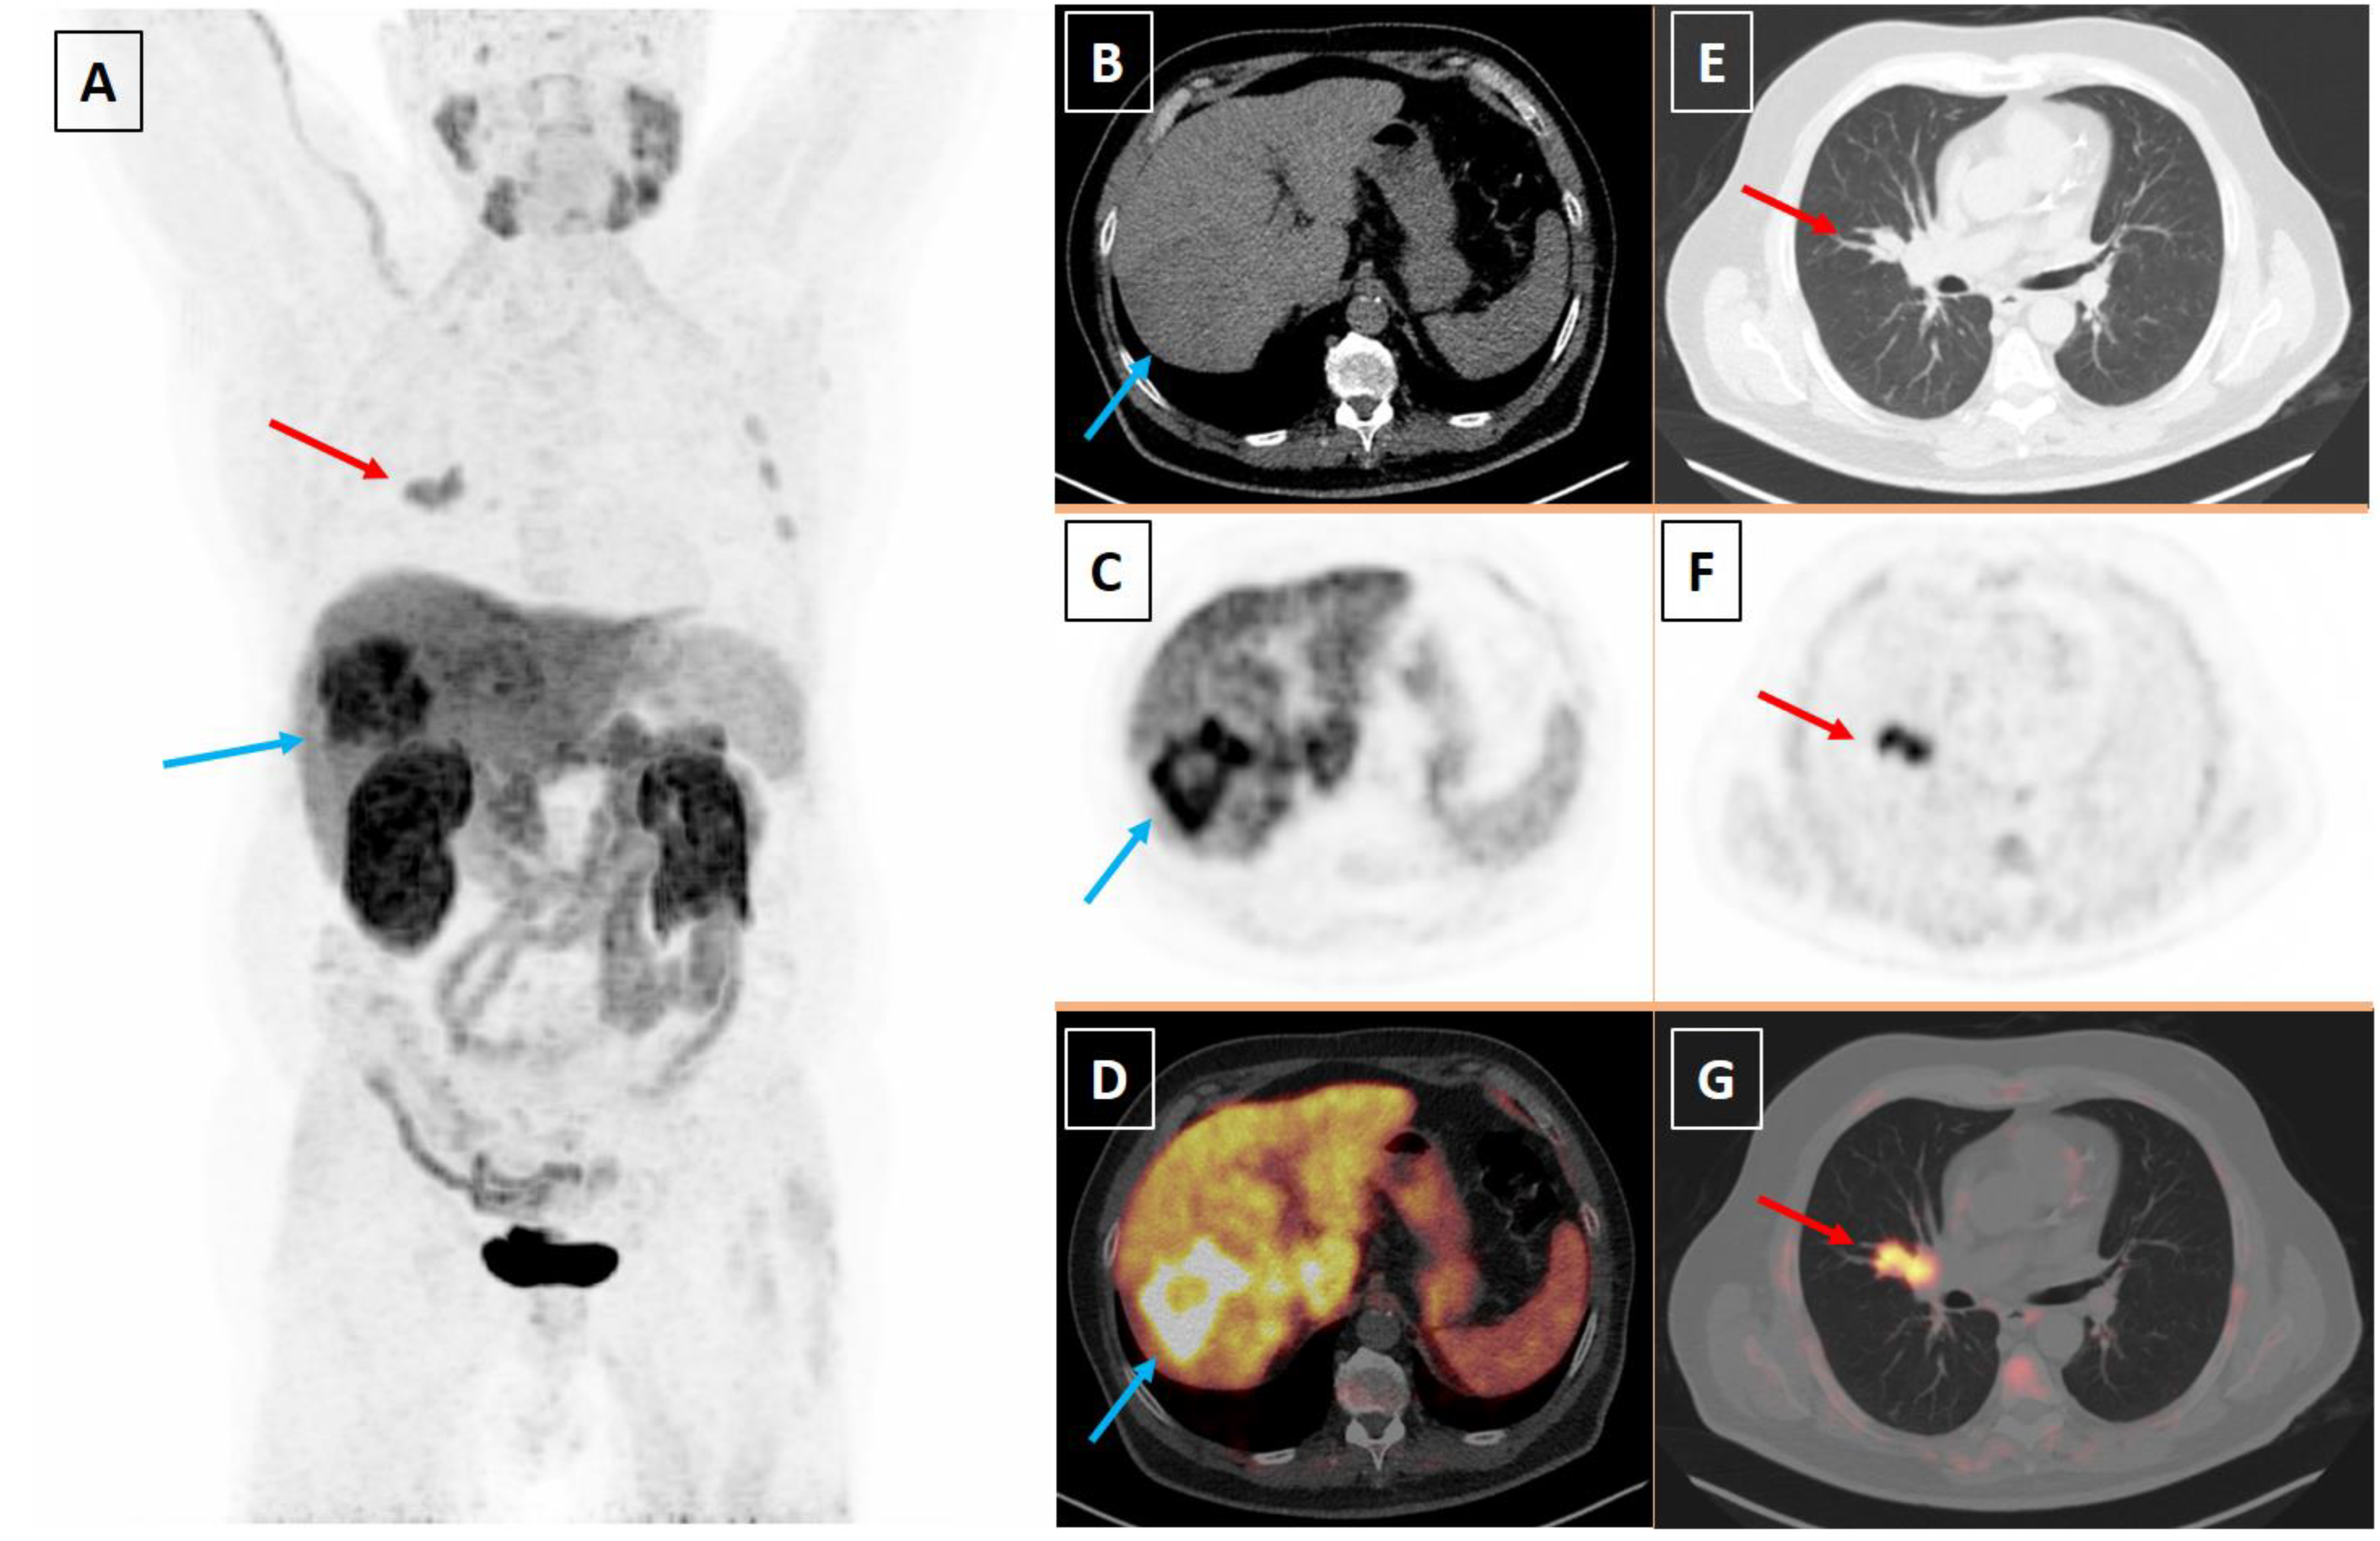

Two Birds with One Stone: Hepatocellular Carcinoma and Small Cell Lung Cancer Imaged with [18F]Fluorocholine Positron Emission Tomography/Computed Tomography